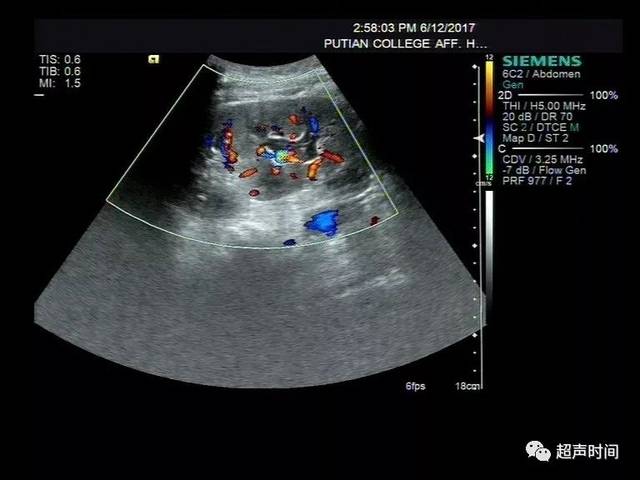

输尿管超声手法图解,输尿管扩张超声图片

输尿管扩张超声图片

超声图像